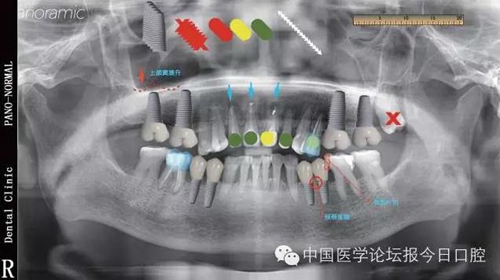

標(biāo)準(zhǔn)化優(yōu)勢(shì)在完整的病例書(shū)寫(xiě)中,最主要的內(nèi)容包括主訴、現(xiàn)病史、檢查、診斷、處理等,其中檢查是非常重要的,也是最復(fù)雜的。在DSD模版里,會(huì)有許多不同顏色,不同形狀的圖標(biāo),這些圖標(biāo)是實(shí)現(xiàn)平臺(tái)標(biāo)準(zhǔn)化的重要工具。

比如在模版中的“圓點(diǎn)”可以有紅色、黃色、綠色等不同顏色,可以把紅色的“圓點(diǎn)”定義為必須拔除的牙齒,綠色“圓點(diǎn)”定義為保留的牙齒,黃色“圓點(diǎn)”定義為介于二者之間的情況;同理,需要根管治療的,需要牙周手術(shù)、種植、正畸牽引的牙齒,我們都可以通過(guò)特定顏色,特定形狀的符號(hào)進(jìn)行標(biāo)注,這樣不僅用一張圖就可以基本涵蓋患者的所有信息,而且避免了文字記錄過(guò)多引起的理解上的混亂及不清晰的弊端。